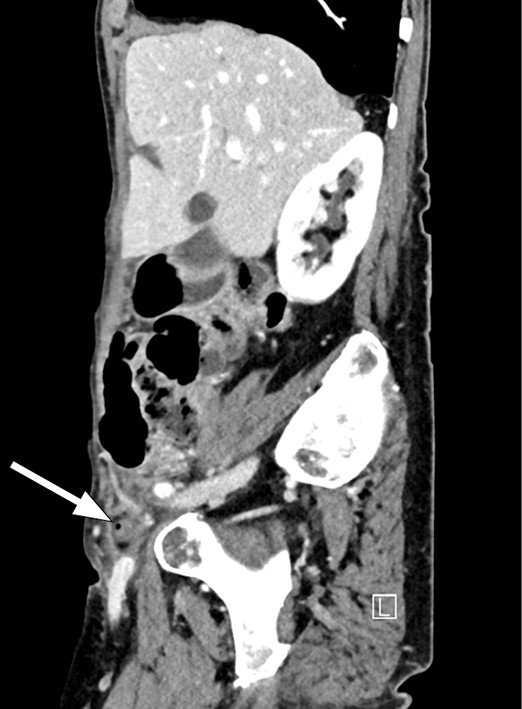

Figure 1 Axial CT scan showing a superficial tubular structure in the right fossa with adjacent adipose tissue remodelling, including thickening of the peritoneum behind. The arrows show (from the left) the femoral artery, femoral vein and appendix.

On account of suspected appendicitis, CT abdomen with contrast was performed and revealed a superficial tubular structure in the right fossa with adjacent adipose tissue remodelling, including thickening of the peritoneum behind. The scan was interpreted as showing an inflamed appendix; the wall of the appendix was also somewhat poorly defined in places, suggesting perforated appendicitis. In addition, a mass was seen in the right inguinal canal with a small gas bubble. Although there was no definite communication with the appendix, it was nevertheless likely that the appendix had herniated into the femoral canal.

The condition is often diagnosed during surgery, but can be detected pre-operatively on CT abdomen. CT is the best modality for visualising de Garengeot's hernia as it can reveal the location and contents of the hernia. The femoral canal is medial to the femoral vein and posterior to the inguinal ligament (1, 4).